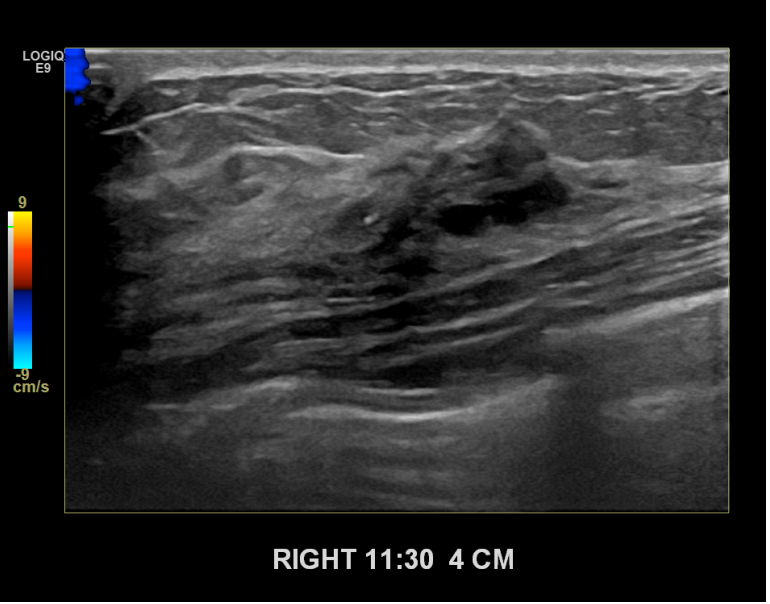

상기환자 경과관찰중이신분으로  우측조직검사를위해  내원하신 40대초반 여성분으로

우측 조직검사 시행해 침윤성암으로 진단되었습니다